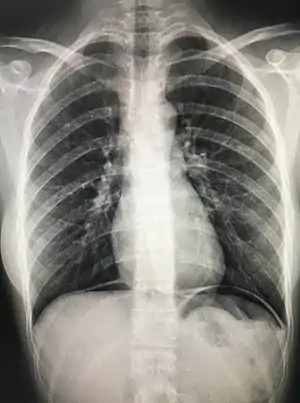

Cupola sign

The cupola sign is seen on a supine chest or abdominal radiograph in the presence of pneumoperitoneum.

It refers to dependent air that rises within the abdominal cavity of the supine patient to accumulate underneath the central tendon of the diaphragm in the midline. It is seen as lucency overlying the lower thoracic vertebral bodies. The superior border is well defined, but the inferior margin is not.